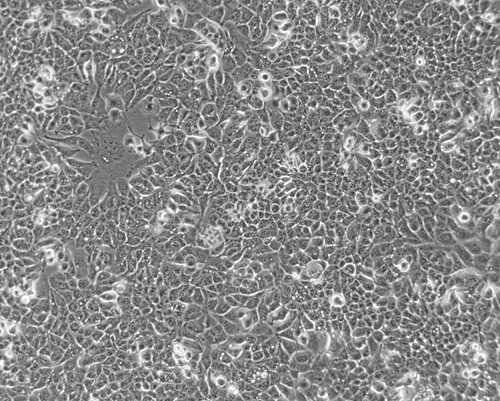

细胞形态: | 上皮细胞样 |

生长特性: | 贴壁生长 |

图片展示